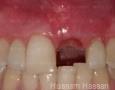

7 Months

9 Months

17 Months